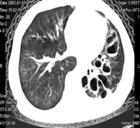

支氣管擴張症可為單側或雙側,大多數位於下葉,但也常發生於右肺中葉和左上肺舌葉.傳統上根據病理和X線表現將其分為圓柱狀,曲張狀或囊狀.然而,這種區分臨床價值不大.最近,病理與高解析度及螺鏇CT特徵的相關已使這種分類趨於棄用.

述症狀和體徵提示支氣管擴張症,胸部X線檢查示肺紋理增深(由於外周支氣管纖維化和管內分泌物瀦留),聚攏(由於肺不張),"軌道征",由於外周支氣管炎症和纖維化),蜂窩狀區,伴有或不伴有液平面的囊性區.偶爾X線也可正常.胸部高解析度CT(HRCT)(1~2mm層厚)已基本上取代支氣管造影.採用10mm校正,擴張的小支氣管可能不被顯影,但HRCT良好的解析度所提供的結果可與支氣管造影媲美,甚至優於後者.廣泛採用HRCT顯示支氣管擴張症要比依靠臨床和胸片作出的診斷更為常見.